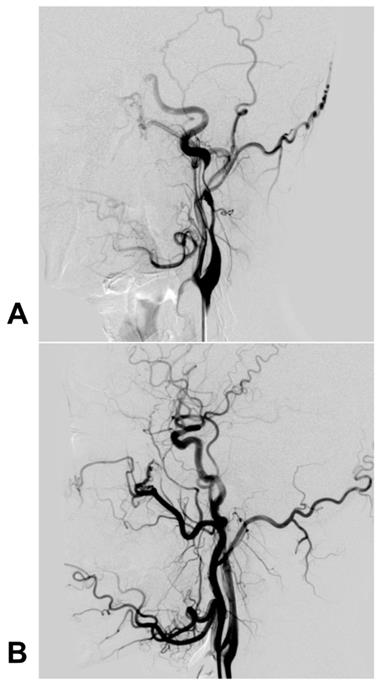

For pseudoaneurysms, CAS with/without coil embolization of the aneurysm cavity is a feasible technique [73]. For instance, Kadkhodayan et al. (2005) reported that 9 traumatic carotid dissections with/without associated pseudoaneurysms were effectively treated with CAS; in this report, some pseudoaneurysms were given coiling simultaneously [71]. Currently, there is no consensus on whether coiling is needed during CAS for pseudoaneurysms, but it is reasonable that large and wide-necked coiling should be recommended [74-76]. A typical case is shown in Figure 3.

Figure 3

Carotid stent deployment for traumatic extracranial ICA dissection with severe stenosis. A: The preoperative DSA revealed a long dissection with severe stenosis of the extracranial ICA, and the intracranial blood supply was poorly visible. B: DSA after carotid stenting showed that the extracranial ICA recovered to a normal diameter, and the intracranial blood supply was normal. Abbreviations: DSA: digital subtraction angiography; ICA: internal carotid artery; MRA: magnetic resonance angiography; MCA: middle cerebral artery; PcomA: posterior communicating artery

Int J Med Sci Image